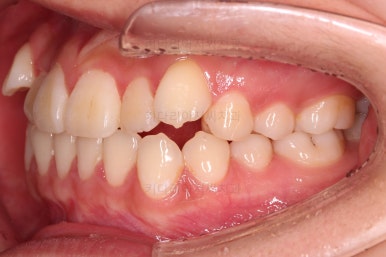

입 안을 보면 밑에 치열이나 다른 부분은 비교적 양호한데 유달리 윗니 송곳니만 위치가 좋지 못하네요.

이번 환자분은 보기에는 송곳니가 덧니라 많이 삐뚤어 있는 것 같지만 치료는 비발치, 즉 발치 없이 진행했는데요.

자칫하면 비발치 시 입이 튀어나오는 경우가 있어요.

삐뚤다는 건 자리가 부족하다는 뜻인데 부족한 자리를 확보 안해주고 억지로 가지런하게 하다보면 치아가 앞으로 튀어나오게 되거든요.

그래서 비발치로 하더라도 본인이 만족할만한 수준까지 입이 나오지 않도록 미니스크류를 병행해서 사용하여 통째로 뒤로 당겨주기로 했습니다.